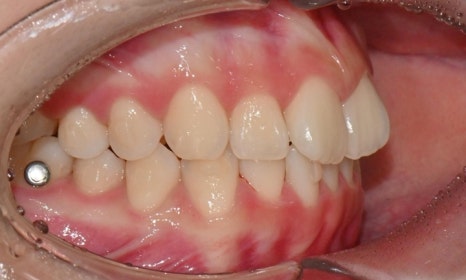

2025.3. 초진 (앞니 경미한 총생과 과개교합) - 연세정원치과

정밀진단 결과 위아래 앞니가 약간 겹쳐 있어 배열이 고르지 않은 상태였으며, 약간의 과개교합이 동반된 상태였습니다. 다만 골격적인 문제나 안모 불균형은 없었고, 측면에서도 돌출감 없이 비교적 안정적인 안모를 유지하고 있었습니다.

이러한 점을 종합적으로 고려해보았을 때 치아 배열의 개선과 교합 조정을 중심으로 한 비발치 교정 치료가 적합한 케이스였습니다. 또한 환자가 고등학생이라는 점, 그리고 학업과 일상 생활에 대한 부담을 최소화하고 싶다는 보호자의 의견을 반영하여, 인비절라인으로 선택하게 되었습니다.

이번 케이스는 인비절라인 Comprehensive로 치료를 진행하였으며, 치아 이동은 과도하지 않게 단계적으로 진행하기 위해 치간삭제를 최소한으로 적용하며 공간을 확보하는 방향으로, 총 33단계의 장치를 통해 치아 이동을 계획하였습니다.